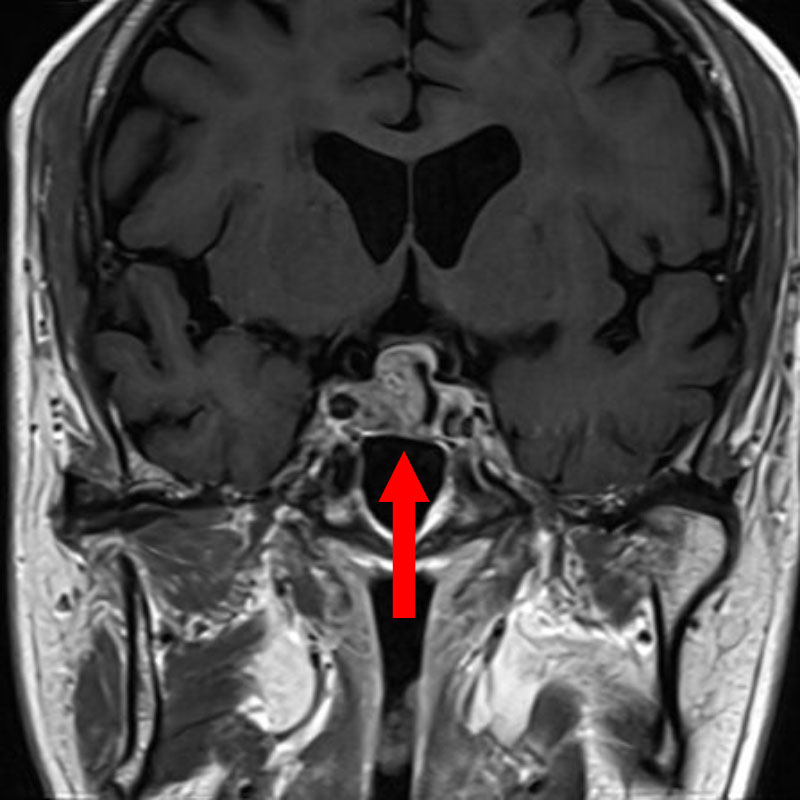

No.’25_107 手術前1

No.’25_107 手術前2